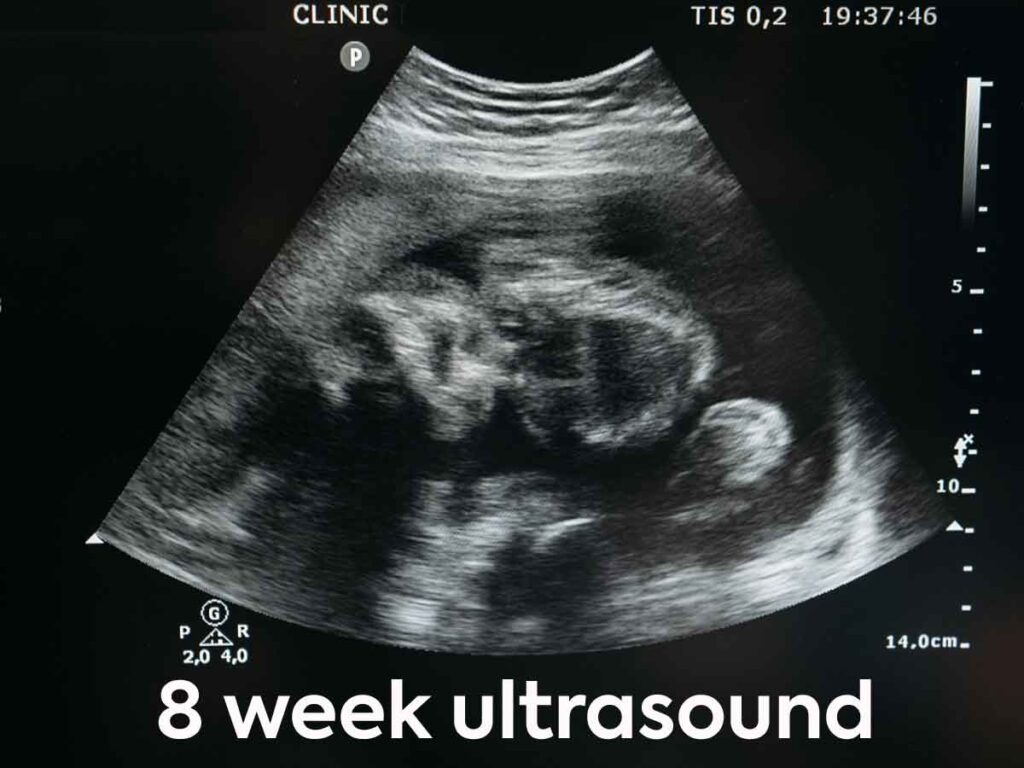

At the 8-week mark, this ultrasound uses an exciting aesthetic journey into the globe of prenatal development. The ultrasound photos reveal an established embryo with distinct functions, showcasing the early development of limbs, a whipping heart, and the start of face attributes.

At this phase, the embryo is still tiny, yet the 8-week ultrasound gives an exceptional level of information, capturing the essence of the blossoming life.

The technology utilized throughout this imaging treatment permits clear visualization of embryonic frameworks, offering understandings into the health and wellness of the pregnancy.

By this point, the embryo is typically about the dimension of a raspberry or around 1.6 centimeters (0.63 inches) in length. Though still small, the established embryo starts to show appreciable attributes.

During the 8th week of pregnancy, critical advancements include the appearance of limb buds, and the first development of essential body organs. The heart is rapidly creating and comes to be a central sight during ultrasound. Doctors analyzed the presence and regularity of the fetal heartbeat, a comforting indication of the embryo’s vigor.

Moreover, the neural tube, which will at some point develop into the brain and spinal cord, remains to form during the 8th week.

The embryo’s head becomes more specified, and little, rudimentary attributes like the eyes and ears begin to form.